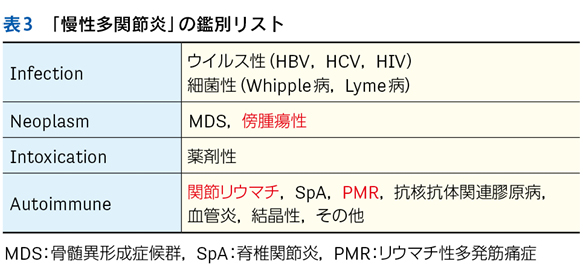

▶ 表3にフレーミングの例をいくつか示す。